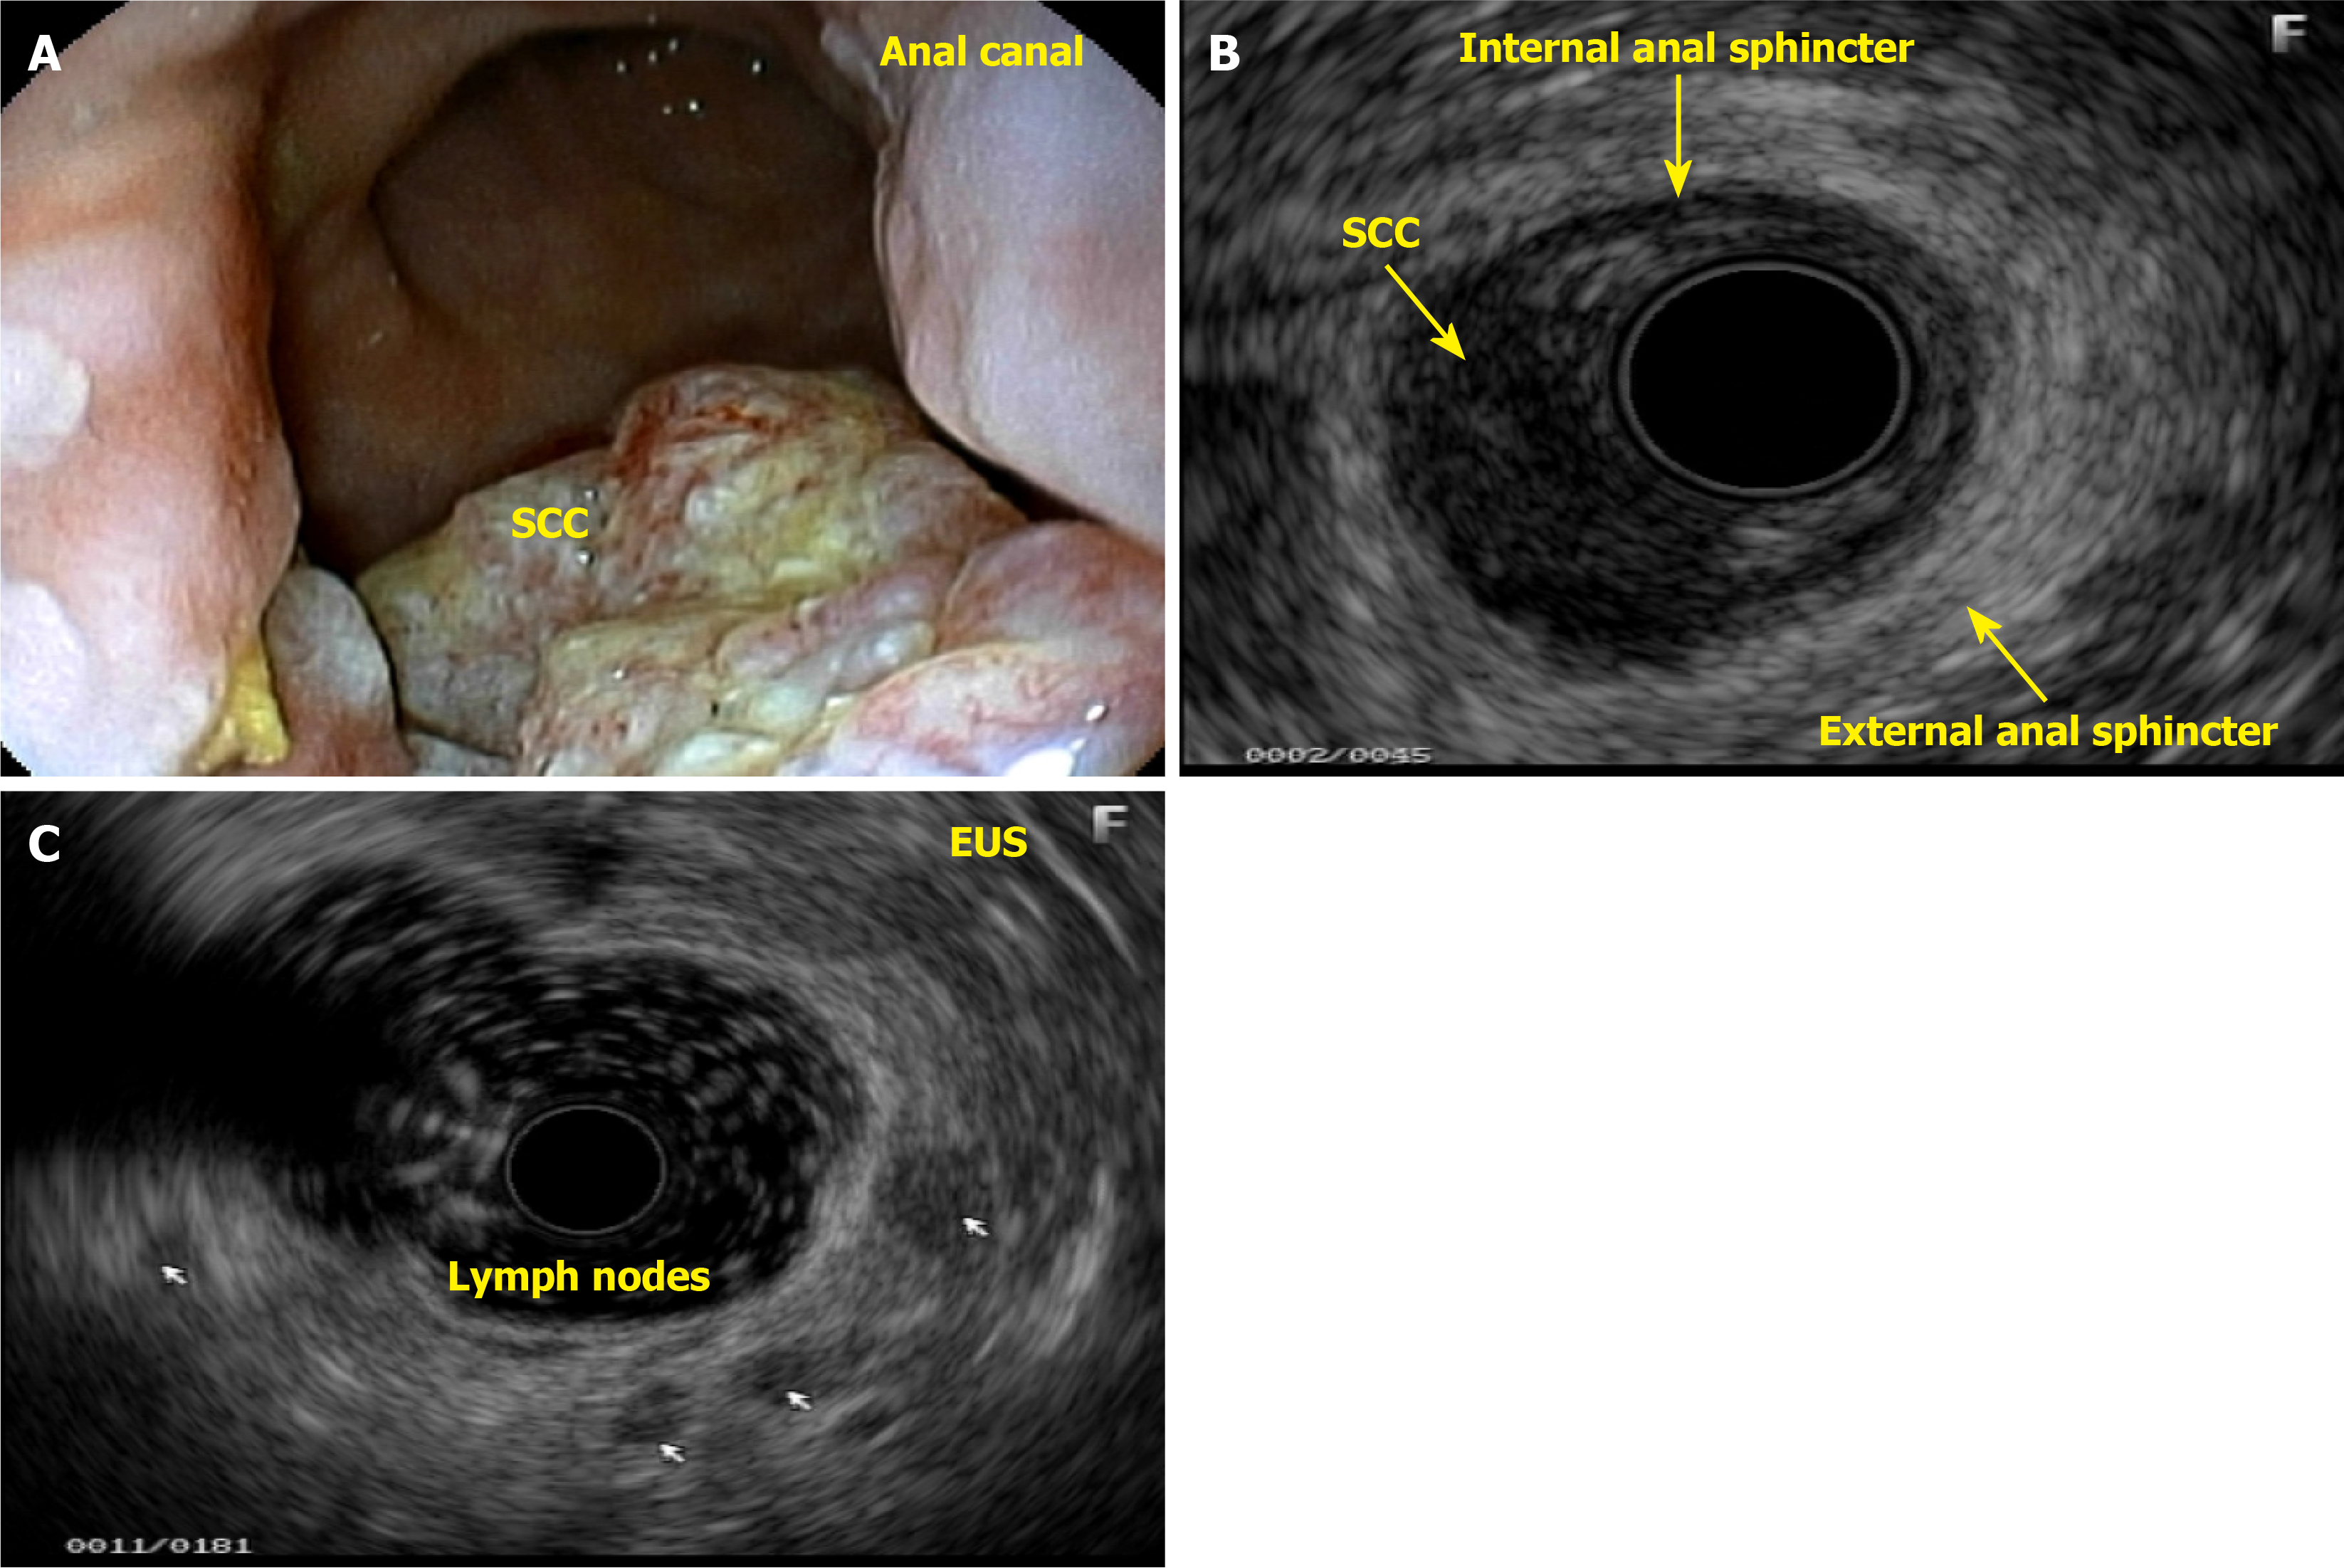

Diagnostic endoanal ultrasound (EAUS) offers several clinically significant benefits in the evaluation and management of anal neoplasms, particularly anal SCC. EAUS provides high-resolution, real-time imaging of the anal canal, allowing for precise assessment of tumor depth, involvement of the internal and external anal sphincters, and perirectal tissue invasion. This detailed local staging is critical for treatment planning, especially in distinguishing early-stage tumors that may be amenable to less aggressive therapy from those requiring more extensive intervention. EAUS is cost-effective, well-tolerated, and can be performed in patients with contraindications to magnetic resonance imaging, such as those with certain implants or severe claustrophobia. However, EAUS is operator-dependent and may be limited in patients with anal stenosis or extensive disease, and its ability to assess lymph node involvement is inferior to that of magnetic resonance imaging. Despite these limitations, EAUS remains a valuable tool for initial staging, treatment planning, and posttreatment surveillance in anal neoplasms, particularly when high-resolution assessment of the anal sphincter complex and local tumor extent is needed.

This patient complained of bleeding during bowel movements, and a colonoscopy revealed a small, ulcerated lesion in the anal canal. A histological study revealed SCC (Figure 10A and B). Patients with HPV-related lesions can have their evaluation extended through the appropriate use of dyes and targeted biopsies, and lesions can be properly resected immediately without the need for a new appointment, which can take too long, thereby eliminating the chance of early cure. Many lesions are subtle, small, and challenging to identify. A thorough and close inspection is necessary to detect small nodules and distinct changes in the mucosa of the anal canal (Figure 10C and D). The colonoscopist can also collect material via brush cytology and request laboratory tests when there is a suspicion of an STI.